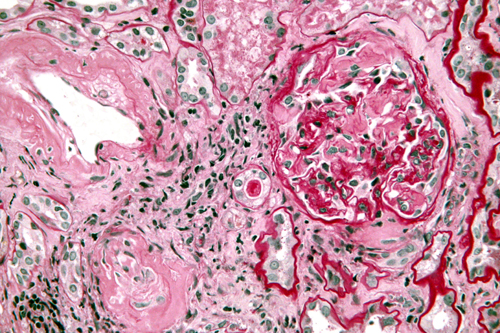

Amyloidosis is a rare disease that occurs when amyloid proteins are deposited in tissues and organs. Amyloid proteins are abnormal proteins that the body cannot break down and recycle, as it does with normal proteins. When amyloid proteins clump together, they form amyloid deposits. The buildup of these deposits damages a person’s organs and tissues. Amyloidosis can affect different organs and tissues in different people and can affect more than one organ at the same time. Amyloidosis most frequently affects the kidneys, heart, nervous system, liver, and digestive tract. The symptoms and severity of amyloidosis depend on the organs and tissues affected.

The kidneys are the organs most commonly affected by primary amyloidosis. Amyloid deposits damage the kidneys and make it harder for them to filter wastes and break down proteins. When the kidneys become too damaged, they may no longer be able to function well enough to maintain health, resulting in kidney failure. Kidney failure can lead to problems such as high blood pressure, bone disease, and anemia—a condition in which the body has fewer red blood cells than normal.